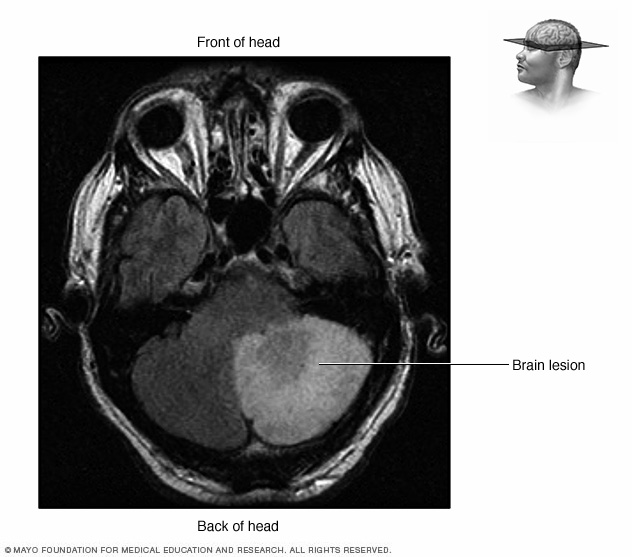

Lista muestra hermosas imágenes de resonancia magnética cerebral normal y anormal dinosenglish.edu.vn para que puedas explorar más en detalle.

resonancia magnética cerebral normal y anormal Pin en NEUROCIENCIAS resonancia magnética de cerebro Resonancia magnética (RM) de cerebro, corte axial ponderado en T2: la … VIDEO Nueva mancha en la Resonancia

Engineer Team : RESONANCIA MAGNETICA Magnetic Resonance Imaging – Clinical Images Hallazgos por resonancia magnética cerebral de nuestro paciente. M, 21 … Imágenes por resonancia magnética anormales como predictoras de mal … Imágenes por resonancia magnética anormales como predictoras de mal … Lesiones en resonancia magnética (RM) del encéfalo y la médula espinal … Pin en Resonancia Magnética del Encéfalo A) Resonancia magnética cerebral (RMC) mostrando infartos en … Caso 1: Edema cerebral visualizado mediante RM. (A) Secuencia T1 plano … Rascacielos dormir pasta tac y resonancia diferencias retrasar … Pin on Apuntes de Enfermería y T.C.A.E Resonancia magnética cerebral secuencia T2, que muestra lesión … Meningitis aguda en la enfermedad de Behçet | Reumatología Clínica Resonancia magnética coronal normal del cerebro Fotografía de stock – Alamy Imágenes de resonancia magnética, la imagen de la cabeza en diferentes … Resonancia magnética cerebral A) protocolo T1 sagital (Caso 1). Se … Resonancia magnética cerebral. Secuencia T1 corte sagital. Atrofia … Resonancia magnética de cerebro, cortes axiales, secuencias T2. Señal … Resonancia magnética de cráneo. A y B) Cortes axiales FLAIR … Resonancia magnética (RM) de cerebro, corte axial ponderado en T2: la … RM cerebral: Interpretación paso a paso | Kenhub Resonancia magnética de cerebro, cortes axiales, secuencias T2. Señal … De Resonancia Magnética De Cerebro Foto de archivo – Imagen de arteria … Top 107+ Imagenes de resonancia cerebral normal – Destinomexico.mx -Imagen por resonancia magnética del cerebro. a) Cortes sagital y axial … resonanCia magnétiCa Cerebral donde se observa hiperintensidad a nivel … MRI (Imagen de resonancia magnética) – Tomografía computarizada de la … Meningioma – NCI Imágenes por resonancia magnética coloreadas del cerebro sano del … Resonancia magnética cerebral en secuencia FLAIR, que muestra lesiones … Contraste resonancia magnetica cerebral – senturinthegreen Relación de los espacios de Virchow-Robin con la enfermedad de … Gliomatosis cerebral – Instituto Nacional del Cáncer Pin en Neurology. Recomendaciones para la utilización e interpretación de los estudios de … Fotografía De La Proyección De Imagen De Resonancia Magnética Del … atmósfera Dirigir Cumplir anatomia resonancia magnetica Desarrollar … Pin en #MEDICINA,#SALUD Resonancia magnética de la nasofaringe De Resonancia Magnética De Cerebro Foto de archivo – Imagen de polilla … Atrofia cortical global de predominio parietal en la Resonancia … Resonancia magnética cerebral | Download Scientific Diagram Neuroblog: Resonancia magnética cerebral en la trombosis crónica de … De Resonancia Magnética De Cerebro Imagen de archivo – Imagen de … ¿Cuáles son los riesgos de la resonancia magnética? – Integra Salud … Resonancia magnética cerebral al decimocuarto día de ingreso: área … Resonancia magnética. Corte axial mostrando área infartada en el … Resonancia magnética cerebral del paciente AV evidenciando lesiones en … -Ressonância magnética de encéfalo mostrando múltiplas imagens … Resonancia magnética cerebral secuencia FLAIR (Fluid Attenuated … Resonancia magnética cerebral con protocolo de epilepsia, en sección … Resonancia magnética cerebral en corte sagital. Se observa una evidente … Resonancia magnética craneal en la que se evidencian lesiones … Logran visualizar el cerebro a detalle más completo tras una resonancia … Así decide el cerebro la severidad de un castigo De Resonancia Magnética De Cerebro, Imagen de archivo – Imagen de … A) Resonancia magnética cerebral; Secuencia Tof: oclusión de arteria … Un estudio asocia la ansiedad con la aparición rápida del Alzheimer IMÁGENES DE 18 F-PR04.MZ PET FUSIONADA CON RESONANCIA MAGNÉTICA … Imágenes por resonancia magnética anormales como predictoras de mal … Tumores de la región pineal – Instituto Nacional del Cáncer Epilepsia: una historia de voces y fantasmas | Neurología Contribución de las imágenes de resonancia magnética por tensor de … Resonancia magnética secuencia T2 plano coronal de quiste epidermoide … Resonancia Magnética Cerebral del paciente: a. Aumento de… | Download … Resonancia magnética cerebral 2022 Síndrome de hemiconvulsión-hemiplejía-epilepsia. Seguimiento de un caso … Enfoque Radiologico: La resonancia magnética permite detectar lesiones … Resonancia magnética craneal T1 con contraste que muestra angiomatosis … guidewiz – Blog Resonancia magnética cerebral, secuencia SWI. Ribete hipointenso en la … resonAnCiA mAgnétiCA de ColumnA Con gAdolinio. Corte sAgitAl en t1 de … SEMANA 12: FUNDAMENTOS DE RESONANCIA MAGNÉTICA NUCLEAR. INDICACIONES Y … DIAGNÓSTICO DE ESCLEROSIS MÚLTIP Magnetic resonance imaging of the brain – Alchetron, the free social … Resonancia magnética de órbitas | Instituto Radiológico Dr. E Castillo Alteración de la marcha en un paciente post-trasplante hepático Resonancia magnética cerebral de un paciente sano (Ay B) y paciente que … Utilidad de la resonancia magnética craneal para el diagnóstico de la … Resonancia Magnética Del Cerebro El Tumor Cerebral Foto de stock y más … De Resonancia Magnética De Cerebro Imagen de archivo – Imagen de … ABDALLA RADIOLOGIA: NEURINOMA ACUSTICO Atrofia cortical global de predominio parietal en la Resonancia … Resonancia Magnética : Producción de la imagen MRI Brain Scan — Stock Photo © Bunyos30 #18724051 Mri (imagen de resonancia magnética) Monitor con imagen de captura de … Tomografía computarizada vs resonancia magnética: diferencia y … Tumores Cerebrales – Unidad de Neurocirugía RGS Resonancia magnética de la columna, sección sagital. Observe los discos … La resonancia magnética, una técnica imprescindible en el diagnóstico … Perfusión Cerebral por Resonancia Magnética | ¿Qué es? ¿Necesita Contraste? Resonancia Magnética Cerebro A: resonancia magnética, T2 coronal preoperatoria; se observa lesión en … Resonancia magnética cerebral — Foto de stock © Bunyos30 #27340623 La resonancia magnética se perfila como detector de mentiras | Futuro … Resonancia magnética cerebral en T1 con gadolinio, cortes axial (a … MRI brain : show brain tumor at right parietal lobe of cerebrum — Stock … NEUROIMÁGENES EN ENFERMEDAD DE PARKINSON: ROL DE LA RESONANCIA …